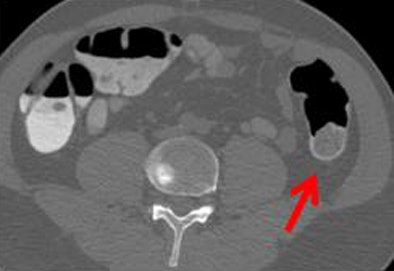

| Poor quality (1, above) means there is significant stool that is incompletely tagged; average (2, below) denotes that some incompletely tagged stool is present; and medium (3, bottom image) represents good overall quality with some stool that is not completely tagged. Superior quality (4) is generally not obtained in reduced-prep regimens. |